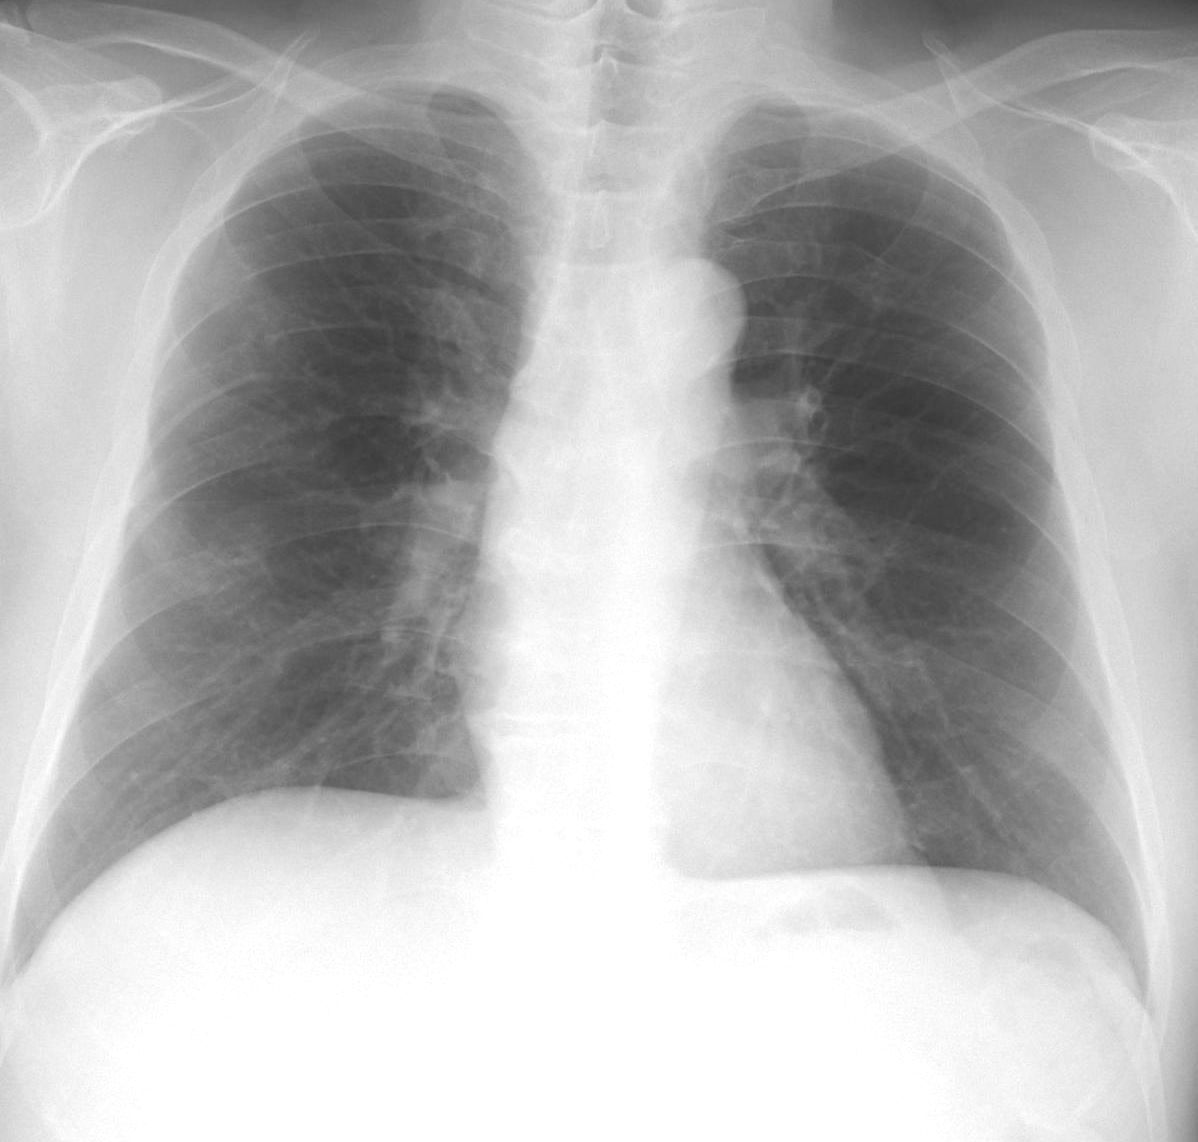

肺野の含気過多があり細気管支炎様のレントゲン像だが、同時に上縦隔右気管支上の部分が反対側の左と比べてやや白く透過性が悪くなっている。このような場合気管支S1もしくはS2の浸潤影初期のことがある。

5日後に確認したレントゲン像を下に提示する。